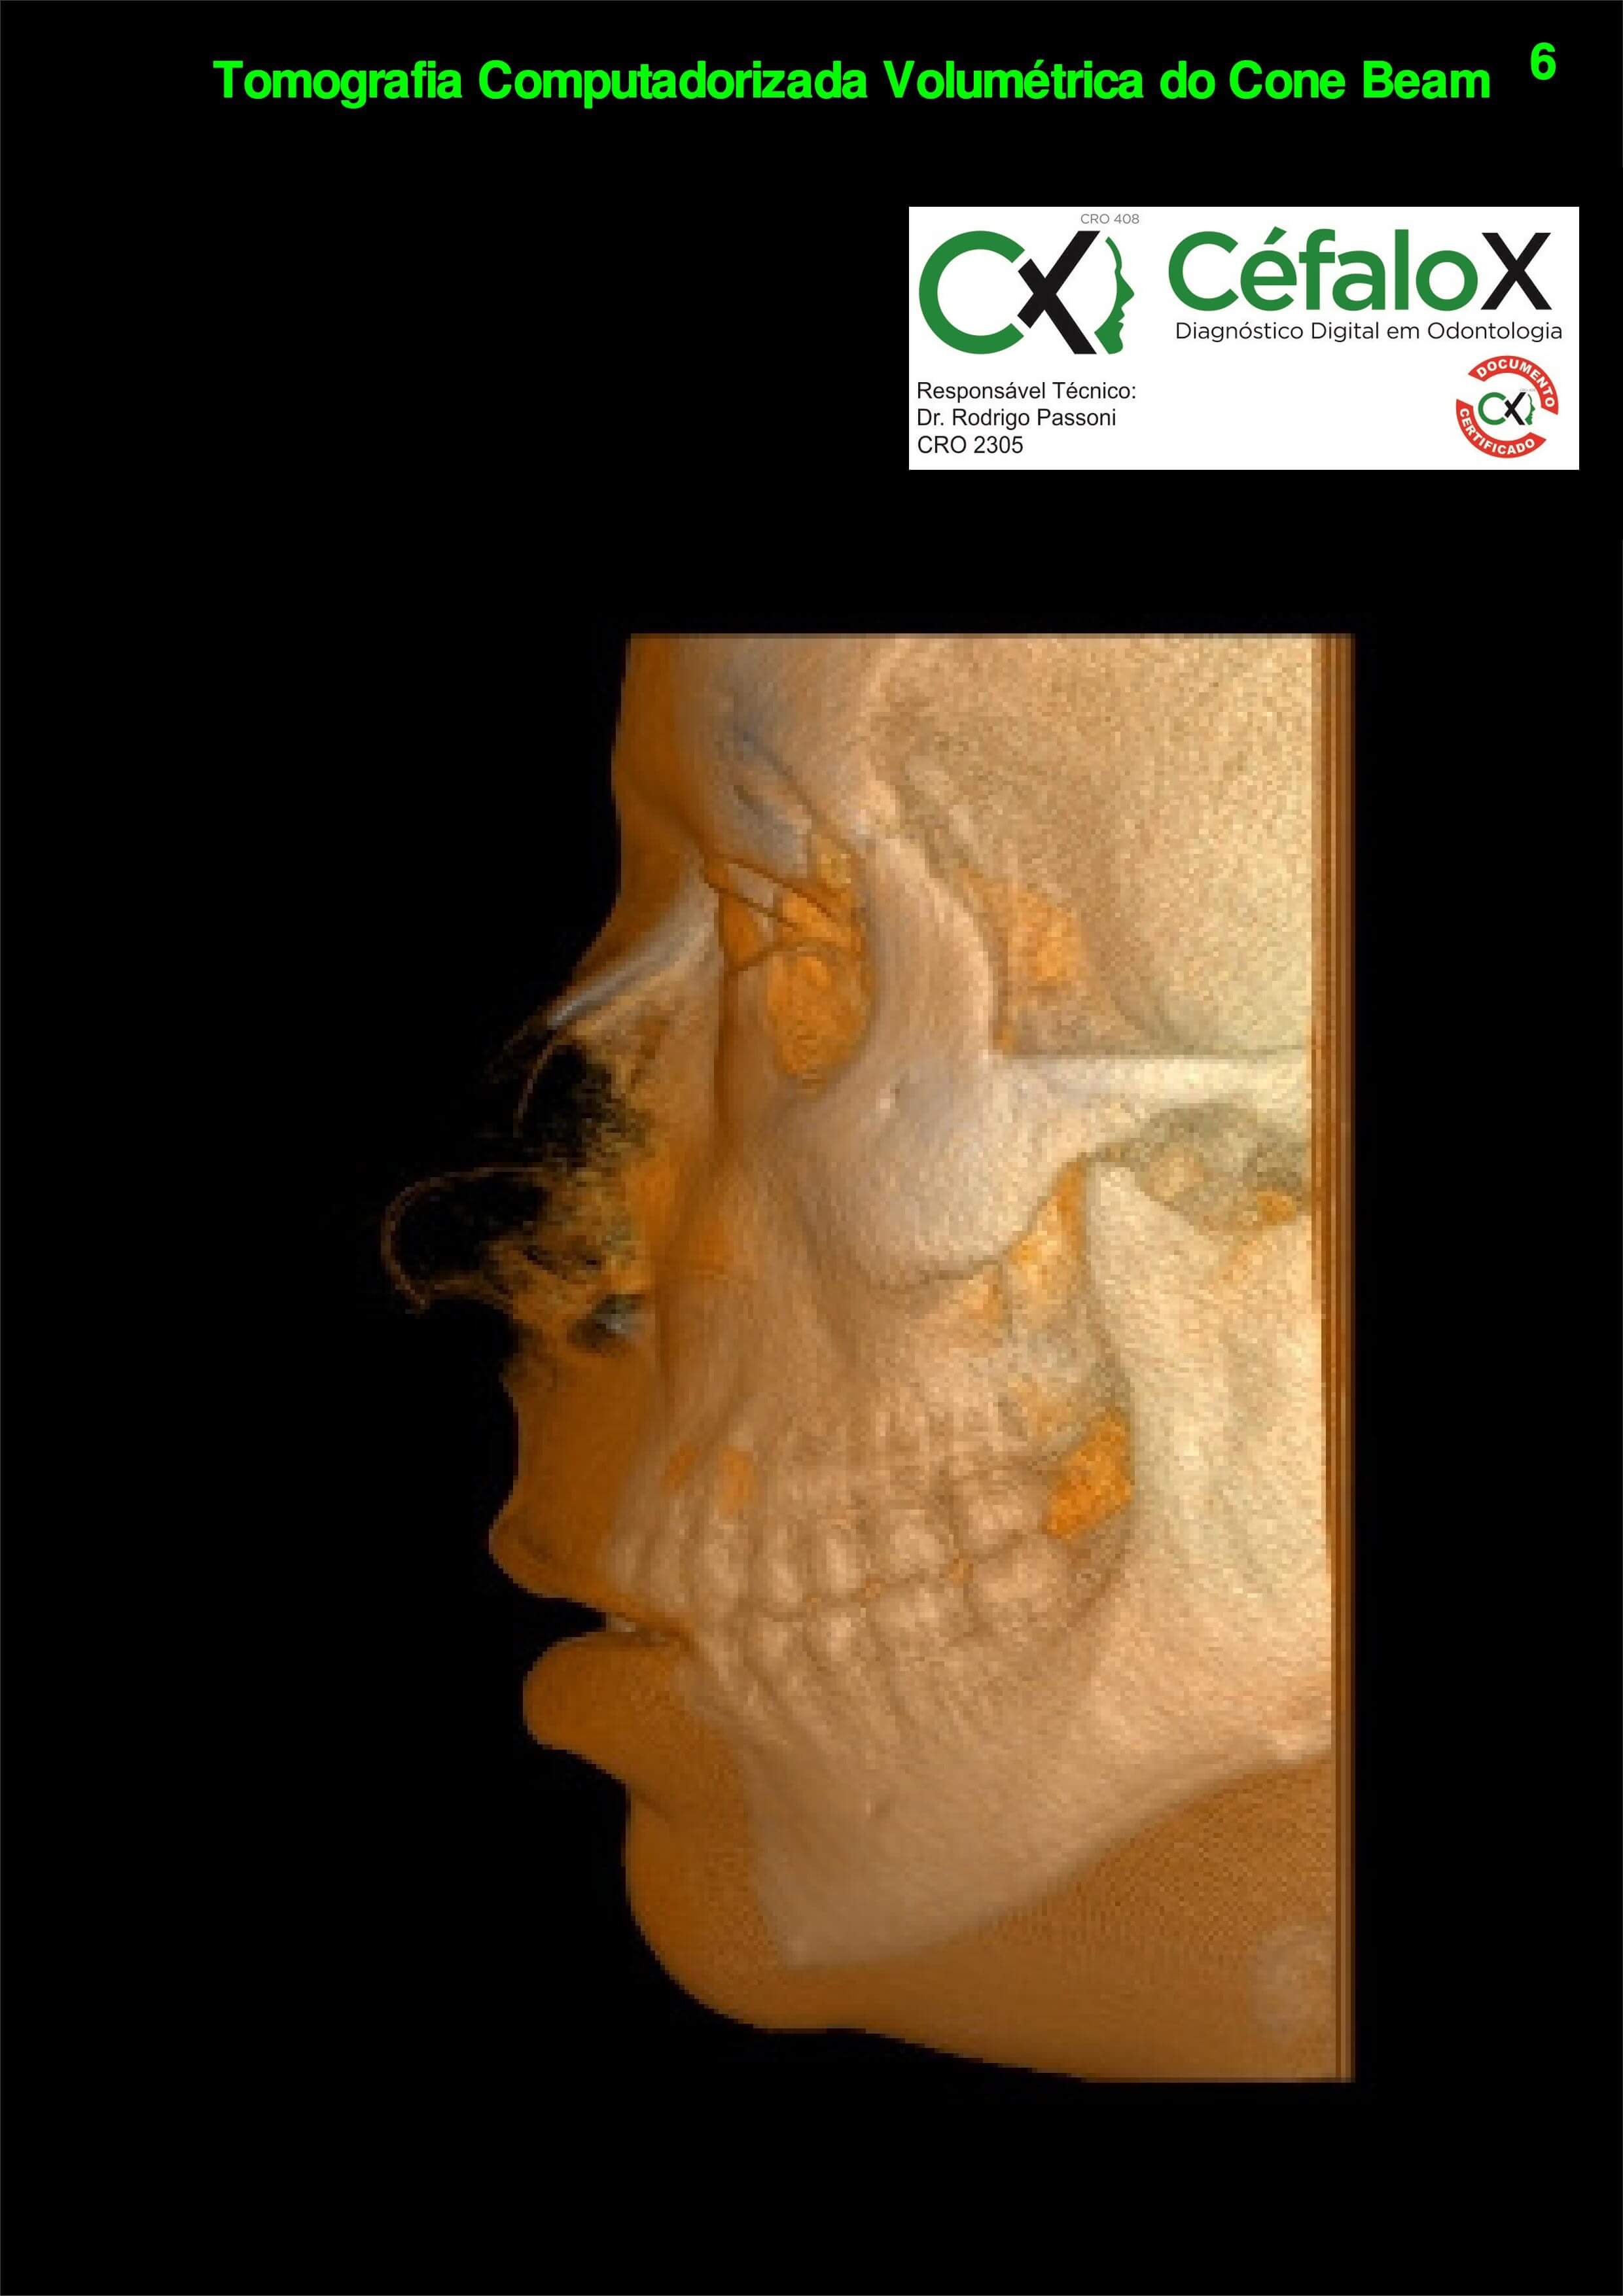

TC de face (do Hióide à Glabela), reconstrução 3D do tecido ósseo, radiografia panorâmica, telerradiografia lateral com traçado, cortes transversais e axial de maxila e mandíbula e arquivo DICOM- entregue em pasta de Pvc.

TC de face (do Hióide à Glabela), reconstrução 3D do tecido ósseo, radiografia panorâmica, telerradiografia lateral e frontal com traçado, cortes transversais e axial de maxila/mandíbula e arquivo DICOM – entregue em pasta de Pvc.

TC de face (do Hióide à Glabela), reconstruções 3D do tecido mole/ósseo/vias aéreas, radiografia panorâmica, telerradiografia lateral e frontal com traçado, cortes transversais e axial de maxila/mandíbula, ATM e arquivo DICOM – entregue em pasta e caixa de Pvc.